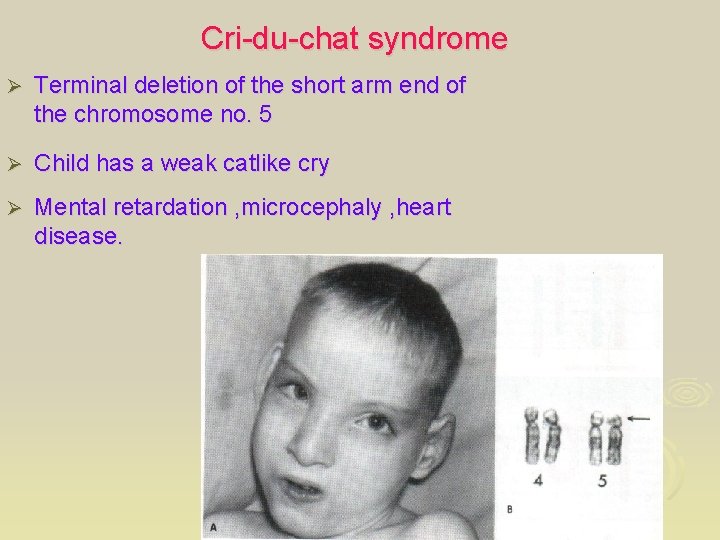

Cri-du-chat syndrome Ø Terminal deletion of the short arm end of the chromosome no. 5 Ø Child has a weak catlike cry Ø Mental retardation , microcephaly , heart disease.